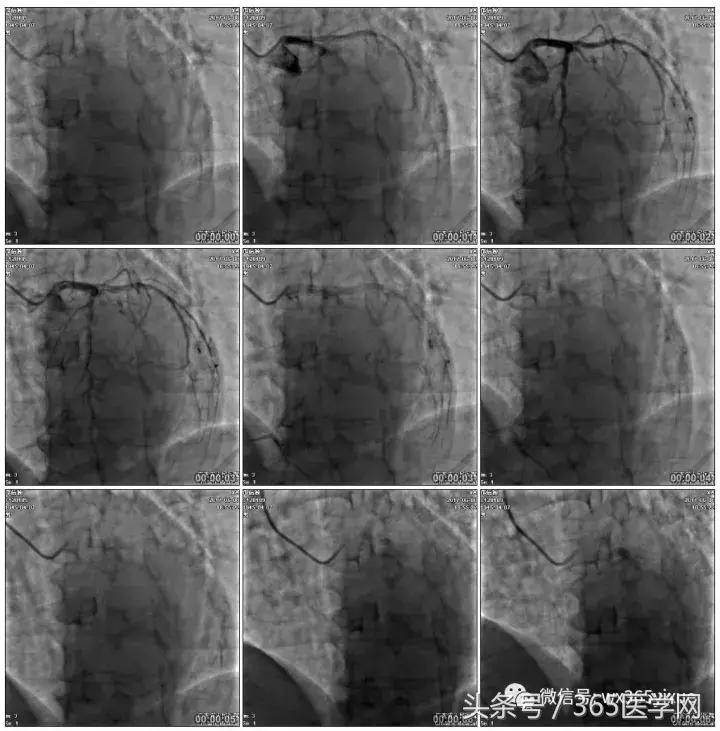

RCA闭塞段球囊扩张后IVUS

支架术后造影结果

支架术后IVUS